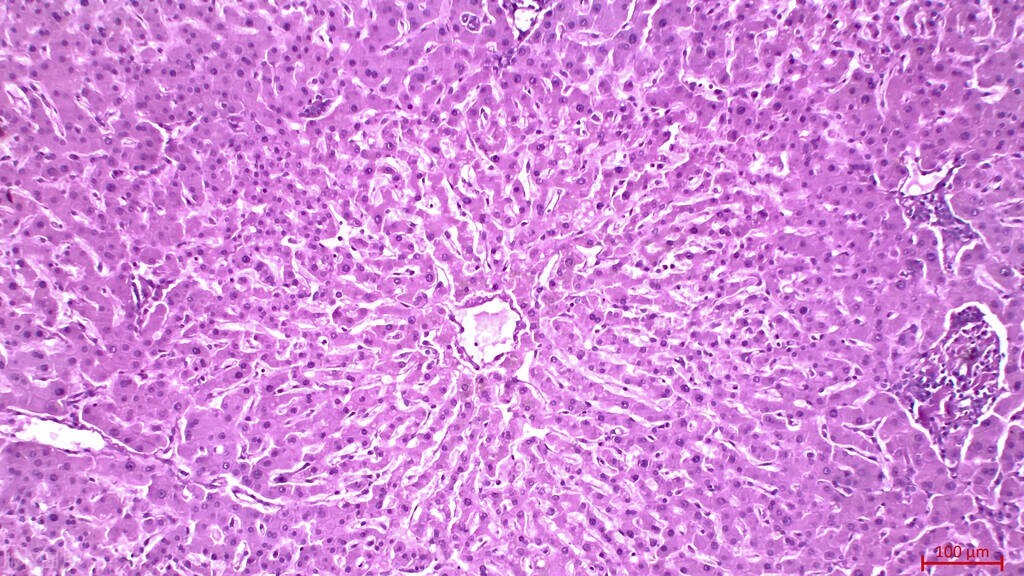

1、诱导肝癌细胞凋亡。 细胞凋亡是维持体内环境稳定和组织器官正常生理功能的重要机制之一,肿瘤的形成与凋亡受阻密切相关,在研究中药抗肿瘤的机制方面,诱导凋亡是中药抗肿瘤的一个重要靶点。

2、抑制癌细胞增殖和诱导分化。 细胞周期失控引起细胞无限增殖是导致癌变的重要原因,抑制肝癌细胞的增殖是治疗肝癌的重要研究方向之一。